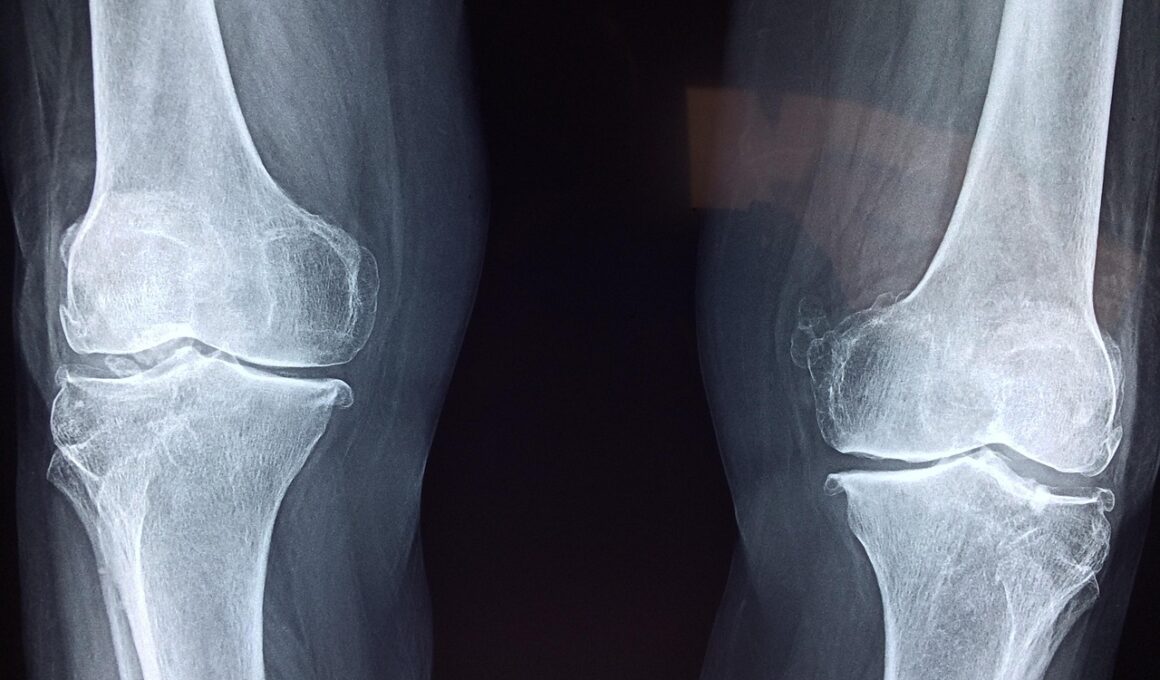

Cycling contributes positively to joint health primarily through its low-impact nature. Regular cycling helps fortify the muscles surrounding the joints, which can mitigate the risk of injury. Strengthened muscles provide better support to the joints, resulting in increased stability and decreased pain during various activities. Additionally, cycling increases synovial fluid production, which lubricates joints, allowing for smoother, pain-free movement. This is particularly beneficial for older adults and those with pre-existing joint conditions. Another significant benefit of cycling is the improved range of motion it promotes. As cyclists pedal, they engage in a fluid motion that helps maintain or improve flexibility in the legs, hips, and knees. By encouraging a full range of motion, cycling assists in combating stiffness and pain often associated with joint issues. Moreover, the cardiovascular workout obtained from cycling is beneficial for maintaining a healthy weight, which is crucial for reducing undue stress on the lower body joints. For anyone looking to enhance their joint health while enjoying physical activity, cycling is an excellent, holistic choice to consider incorporating into their routine.